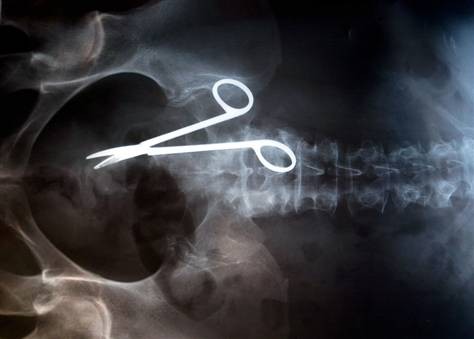

Одним из лидеров недели в Twitter стал хештег #WeirdThingsToPutUpYourAss (Странные штуки, которые суют в задницу). Проктологи со всего мира поделились рентгеновскими снимками содержимого анусов своих пациентов. Выяснилось, что огурец - еще не самое удивительно, что можно обнаружить там, где не светит солнце.